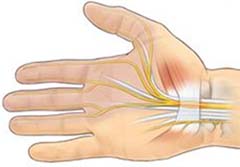

Tunnel carpale

La sindrome del tunnel carpale è la neuropatia da compressione più frequente. Il nervo mediano è compresso a livello del tunnel carpale, quest’ultimo è localizzato prima della piega del polso. Coinvolge principalmente le donne adulte e nel 50% dei casi è bilaterale, anche se generalmente i sintomi sono più gravi in un lato. Una buona valutazione della sintomatologia del paziente e l’esame elettromiografico sono necessari per eseguire una corretta diagnosi. La sindrome del tunnel carpale va differenziata dai sintomi che possono essere causati da un problema a livello del midollo cervicale. L’intervento chirurgico è raccomandato in quei pazienti in cui il dolore dura da più di 6 mesi, per la presenza di parestesie, per la riduzione della sensibilità o per la riduzione della forza.